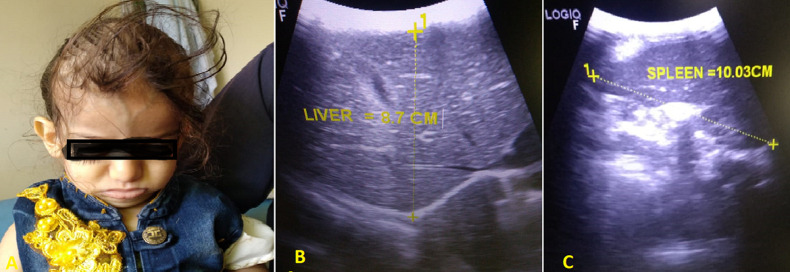

摘要婴儿恶性骨质疏松症是一种罕见的常染色体隐性遗传的骨吸收性疾病。它的特点是由于破骨细胞分化或功能失败导致骨密度增加。IMOP的临床表现从出生或婴儿期开始,根据骨质疏松的类型和程度有不同的环。我们提出了一个3岁的女性病人转介到我们由于慢性贫血六个月前。体格检查显示肝脾肿大,轴向张力低下,视力受损。血液检查显示全血细胞减少和低钙血症。影像学检查显示骨密度普遍增高,干骺端重塑异常,脑萎缩。骨髓穿刺(BMA)显示所有细胞系的干龙头和细胞增多。IMOP的诊断取决于临床、放射学和BMA结果。总之,IMOP是相对罕见的。准确的诊断应通过临床、BMA和放射学检查做出,特别是在资源有限的情况下,正如本病例所做的那样。

Infantile malignant osteopetrosis (IMOP) is a rare bone resorptive disorder with an autosomal recessive inheritance pattern. It is characterized by increased bone density due to osteoclastic failure in differentiation or function. The clinical manifestations of IMOP start at birth or infancy with varied rings according to the type and degree of osteopetrosis. We presented a 3-year-old female patient referred to us due to chronic anaemia six months ago. The physical examination revealed hepatosplenomegaly, axial hypotonia, and visual impairment. Blood investigation revealed pancytopenia and hypocalcemia. Radiologic studies revealed a generalized increase in bone density, abnormal metaphyseal remodelling, and rain atrophy. The bone marrow aspiration (BMA) shows dry tap and hypocellularity of all cell lines. IMOP was diagnosed depending on clinical, radiologic, and BMA results. In conclusion, IMOP is relatively uncommon. Accurate diagnosis should be made through clinical, BMA, and radiologic investigations, especially in a resource-limited setting, as performed in our case.